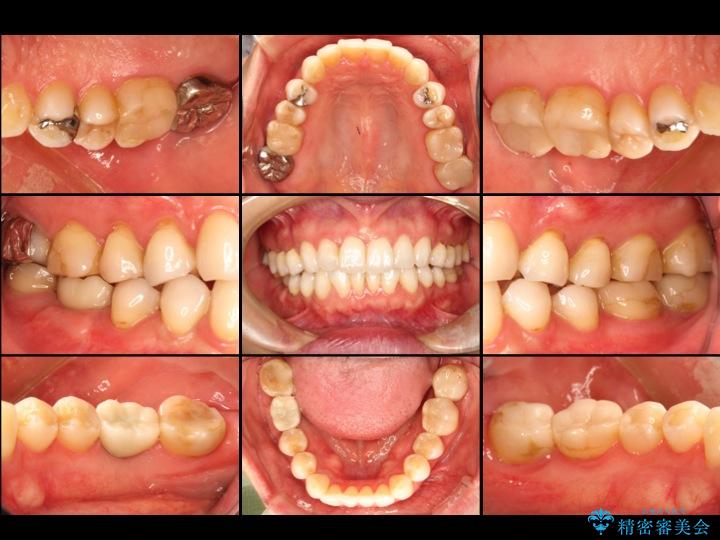

【40代男性】前歯のセラミックと奥歯のインプラント

前歯の見た目と、奥歯でよく噛めない事で来院されました。

- セラミック治療

- セラミック素材を用いた被せ物や詰め物の治療

- インプラント治療

- 顎の骨に人工歯根(インプラント体)を埋め込み、上部構造(人工歯)を装着する治療

- 治療費

- 250万円

- リスク・副作用について

- 天然歯を削ります/硬い素材は天然歯を傷つけてしまう場合があります/かみ合わせや歯ぎしりが強すぎる方はセラミックが割れてしまう可能性があります

- 術後に痛みや腫れ、違和感を伴います/メンテナンスを怠ったり喫煙により、お口の中に大きな悪影響を及ぼすインプラント周囲炎等にかかる可能性があります/糖尿病、肝硬変、心臓病等の場合、インプラント治療ができない可能性があります/高血圧、貧血・不整脈等の場合、インプラント治療後に治癒不全を招く可能性があります